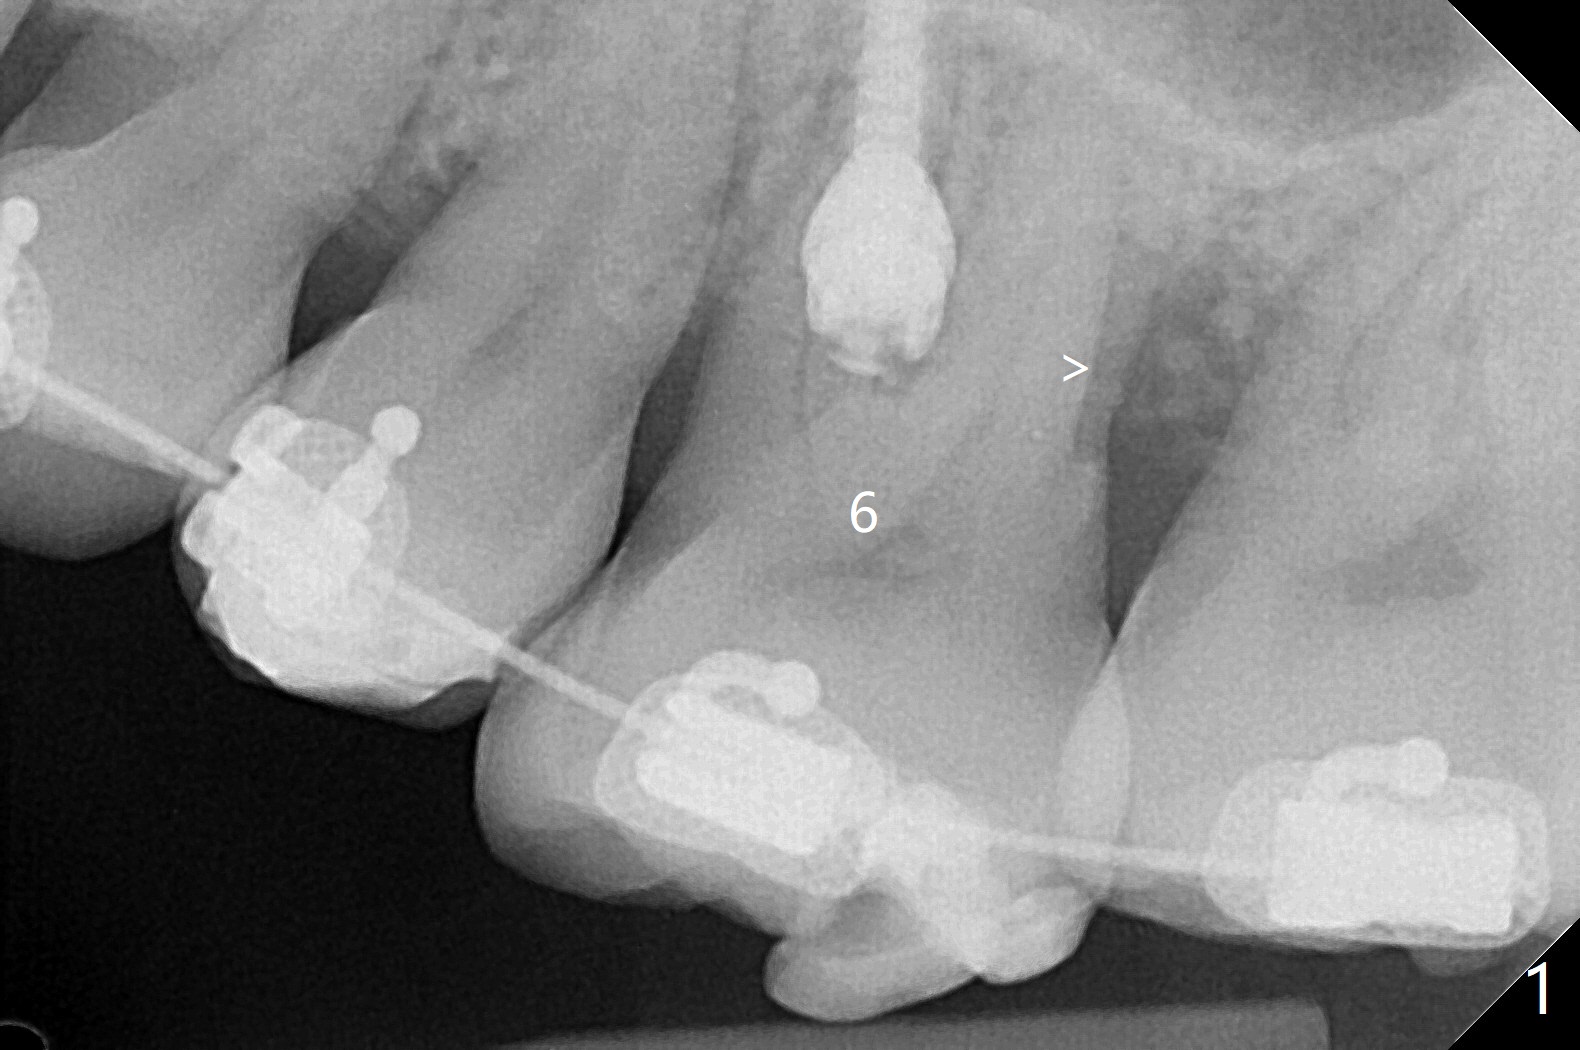

前几周介绍一个矫正砸锅病例,微型植体植入左上6(for intrusion,矫正压低)颊侧远中没有骨质区域,造成局部骨质缺损(图一:>)。颊侧,腭侧牙龈沟切口,翻瓣,清创后,植入粘性骨粉(图二:*,也在颊侧,腭侧植骨),覆盖PRF膜,使用4-0 Monoglyc缝线缝合。对于左下6缺失,原先病人(31岁女)要求前移7,8,初步矫正(2个月内)引起7松动(图三),经过讨论,病人同意拔除8,然后竖直7。拔出后,放置半块胶原塞(控制出血,图四:C),然后植骨(*),最后放置另外半块胶原塞(C),4-0 PGA缝合。术后一个月腭侧放置power chain压低磨牙(图五)。术后2.5个月缺牙间隙大于前磨牙,可以种植,同时7近中植骨(图六:*(粘性骨粉))。整合后利用6作为抛锚继续做7竖直。